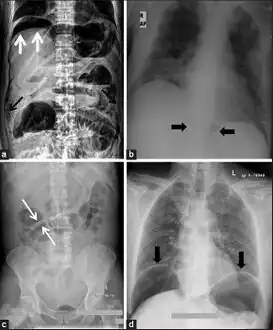

The double wall sign marks the presence of air on both sides of the intestine.[27] However, a false double wall sign can result from two loops of bowel being in contact with one another.[28] The sign is named after Leo George Rigler.[29] It is not the same as Rigler's triad.

The football sign is when the abdomen appears as a large oval radiolucency reminiscent of an American football on a supine projectional radiograph.[30] The football sign is most frequently seen in infants with spontaneous or iatrogenic gastric perforation causing pneumoperitoneum. It is also seen in bowel obstruction with secondary perforation, as in Hirschprung disease, midgut volvulus, meconium ileus and intestinal atresia. Iatrogenic causes like endoscopic perforation may also give football sign.

The Cupola sign is seen when air is accumulated under the central tendon of the diaphragm.[31]

a) X-ray of abdomen, showing subdiaphragmatic free air, air outlining the properitoneal fat stripe black arrows b) Cupola sign arrowheads c) Rigler's sign d) chest radiograph showing free air under the diaphragms

Pneumoperitoneum seen on X-ray with the patient lying on his left side.

Double wall sign. This is a secondary sign of pneumoperitoneum. Patient is supine, and air within the abdomen and lumen of the bowel accentuate both sides of the bowel wall.- Ultrasound finding of pneumoperitoneum known as "peritoneal stripe sign"[32]